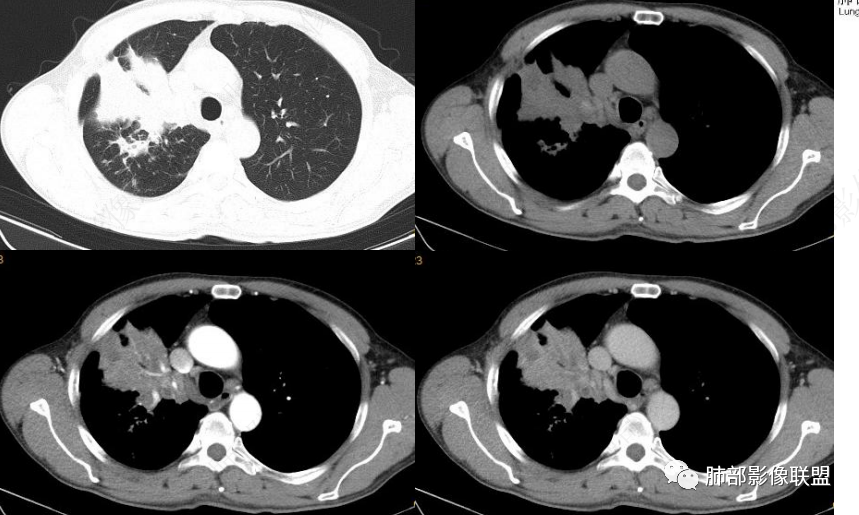

如果炎性大家考虑啥?问个问题:大家定在上叶没问题,哪个段?

南边:

各段都受累

尖段为主

就是看不清下面的支气管壁

一般如果炎症,支气管壁会延续过来,

远端粘液栓

一般来说炎性的是近端支气管狭窄,腔内粘液栓

这个支气管壁没显示出来

就怕腔内占位堵塞不全

下图是炎性的

一般支气管狭窄一些,壁弥漫增厚

今天的病例追到这里断了,腔内病灶有强化就不踏实。

这是炎性特点,壁弥漫增厚,腔内粘液栓

这例也是,只是我调节不理想,壁其实也是弥漫增厚,腔狭窄,腔内粘液栓